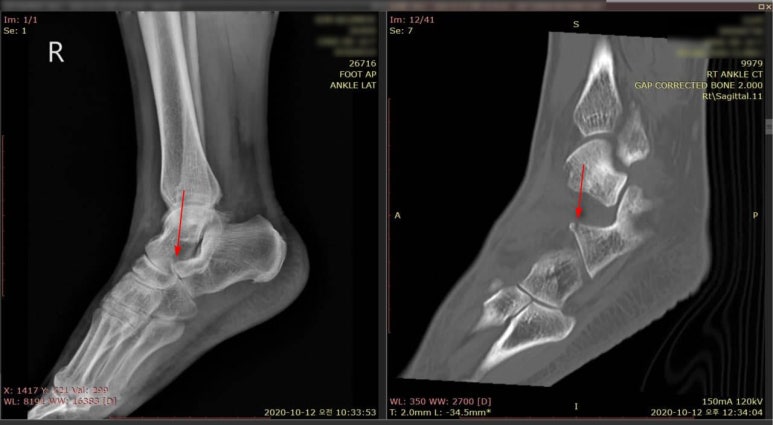

우측 그림의 빨간 화살표가 비전위성 골절 부위입니다. 뼈의 위치는 그대로 있으면서 실금이 간 것입니다.** 노란색 화살표의 골피질이 연결되는 것으로 보아 녹색 화살표는 혈관이 들어가는 자리로 추정됩니다.**

위 환자분은 화곡역 계단에서 발목을 접질린 후 오전 10시33분에 동네 정형외과에서 엑스레이를 찍으셨습니다. 엑스레이상 골절은 없고 인대가 늘어났다고 하여 한의 치료를 받고자 오셨습니다. 걷는데는 전혀 불편함이 없고, 계단을 딛거나 힘이 들어가면 아픕니다. 펜으로 표시한 부위가 다친 부위인데, 눌러보니 자지러지게 아프다고 합니다.

이 곳은 종골의 전방 돌기로 종입방골인대가 붙는 곳입니다. 종입방인대 앞쪽섬유는 두갈래인대(종입방인대 + 종주상인대) 중 하나인데, 여기 인대가 당겨지면서 작은 견열골절이 발생하면 엑스레이에서 골절선이 잘 보이지 않습니다. 확실하게 골절 여부를 확인하기 위해 640 CT를 의뢰하였습니다.

바로 협력병원으로 전원시켜 시행한 640시티에서 종골 전방 돌기의 견열골절로 진단되었습니다.위 그림의 우측 시티에서는 골절이 보이지만 좌측 엑스레이에서는 뼈가 겹쳐서 골절선이 보이지 않습니다. 떨어져 나간 뼈 조각은 본래 뼈와 붙지 않고 인대 내부에 남아있게 됩니다.** > 수술을 꼭 해야 하나요? 골절 부위와 형태, 전위 정도, 관절 침범 여부에 따라 다릅니다. 예를 들어 손목의 주상골 골절(scaphoid fracture)도 엑스레이에서 잘 보이지 않습니다. 그런데 문제는 여기에 골절이 생기면 뼈가 유합되지 않고 괴사되는 경우가 많습니다.**